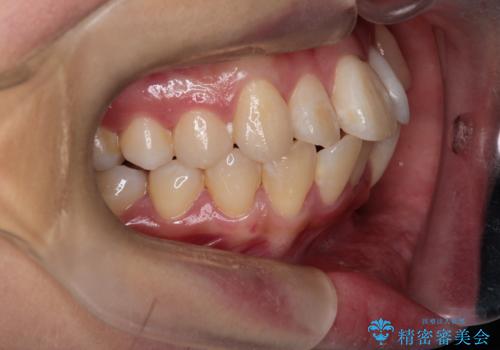

八重歯と正中のズレを解消!目立ちにくいワイヤー矯正で美しい歯並びへ

- 八重歯(叢生)と、上下の歯の中心線(正中)がずれていることを主訴にご来院されました。精密な検査の結果、歯列全体のスペースが大幅に不足しており、八重歯を正しい位置に配列し、正中のズレを改善するためには、上下左右の第一小臼歯を抜歯する必要があると診断。装置には、目立ちにくい審美ワイヤーを使用し、見た目を気にせず、機能性と審美性が完璧に整った咬み合わせを目指す治療計画を立案しました。

八重歯: 突出していた八重歯を歯列内に誘導し、デコボコを解消しました。

正中のズレ: 歯を左右対称に移動させることで、上下の歯の中心線を正確に合わせ、顔全体のバランスも改善しました。